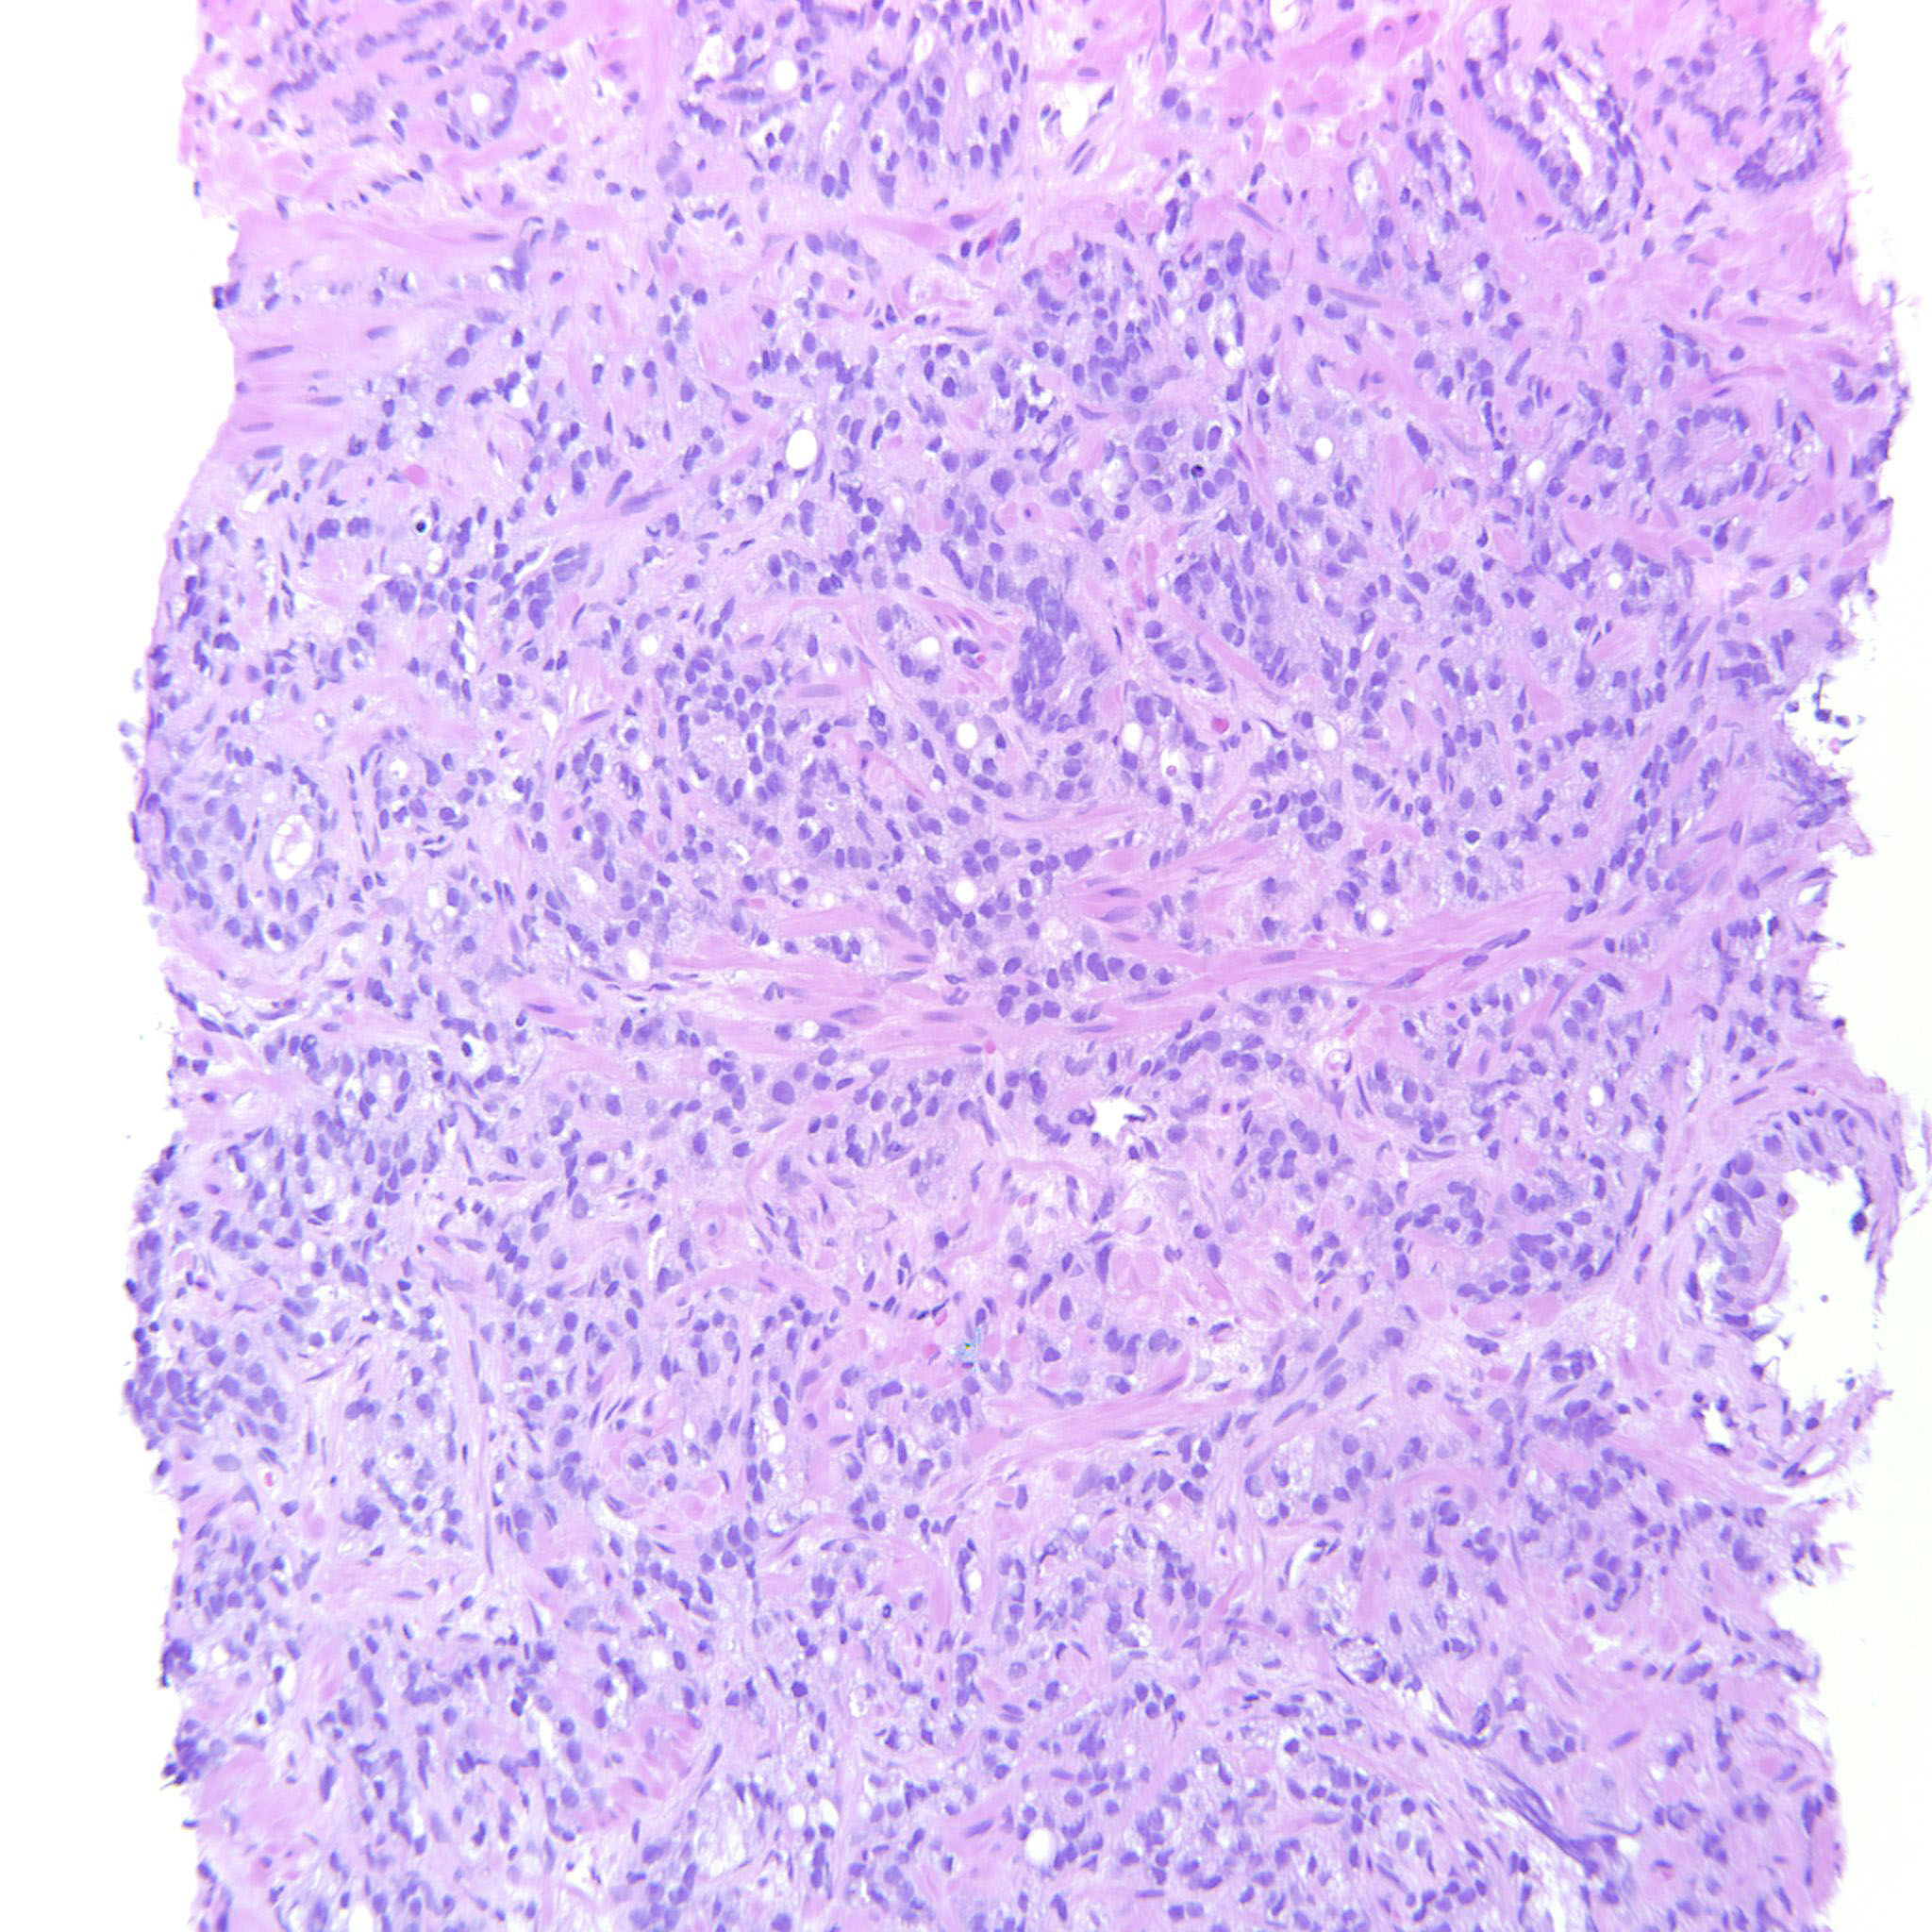

Consensus grade: GS 9-10 (ISUP 5)

Case description (by case creator):

4+5=9 where the GP5 component infiltrates diffusely in strands and single cells.